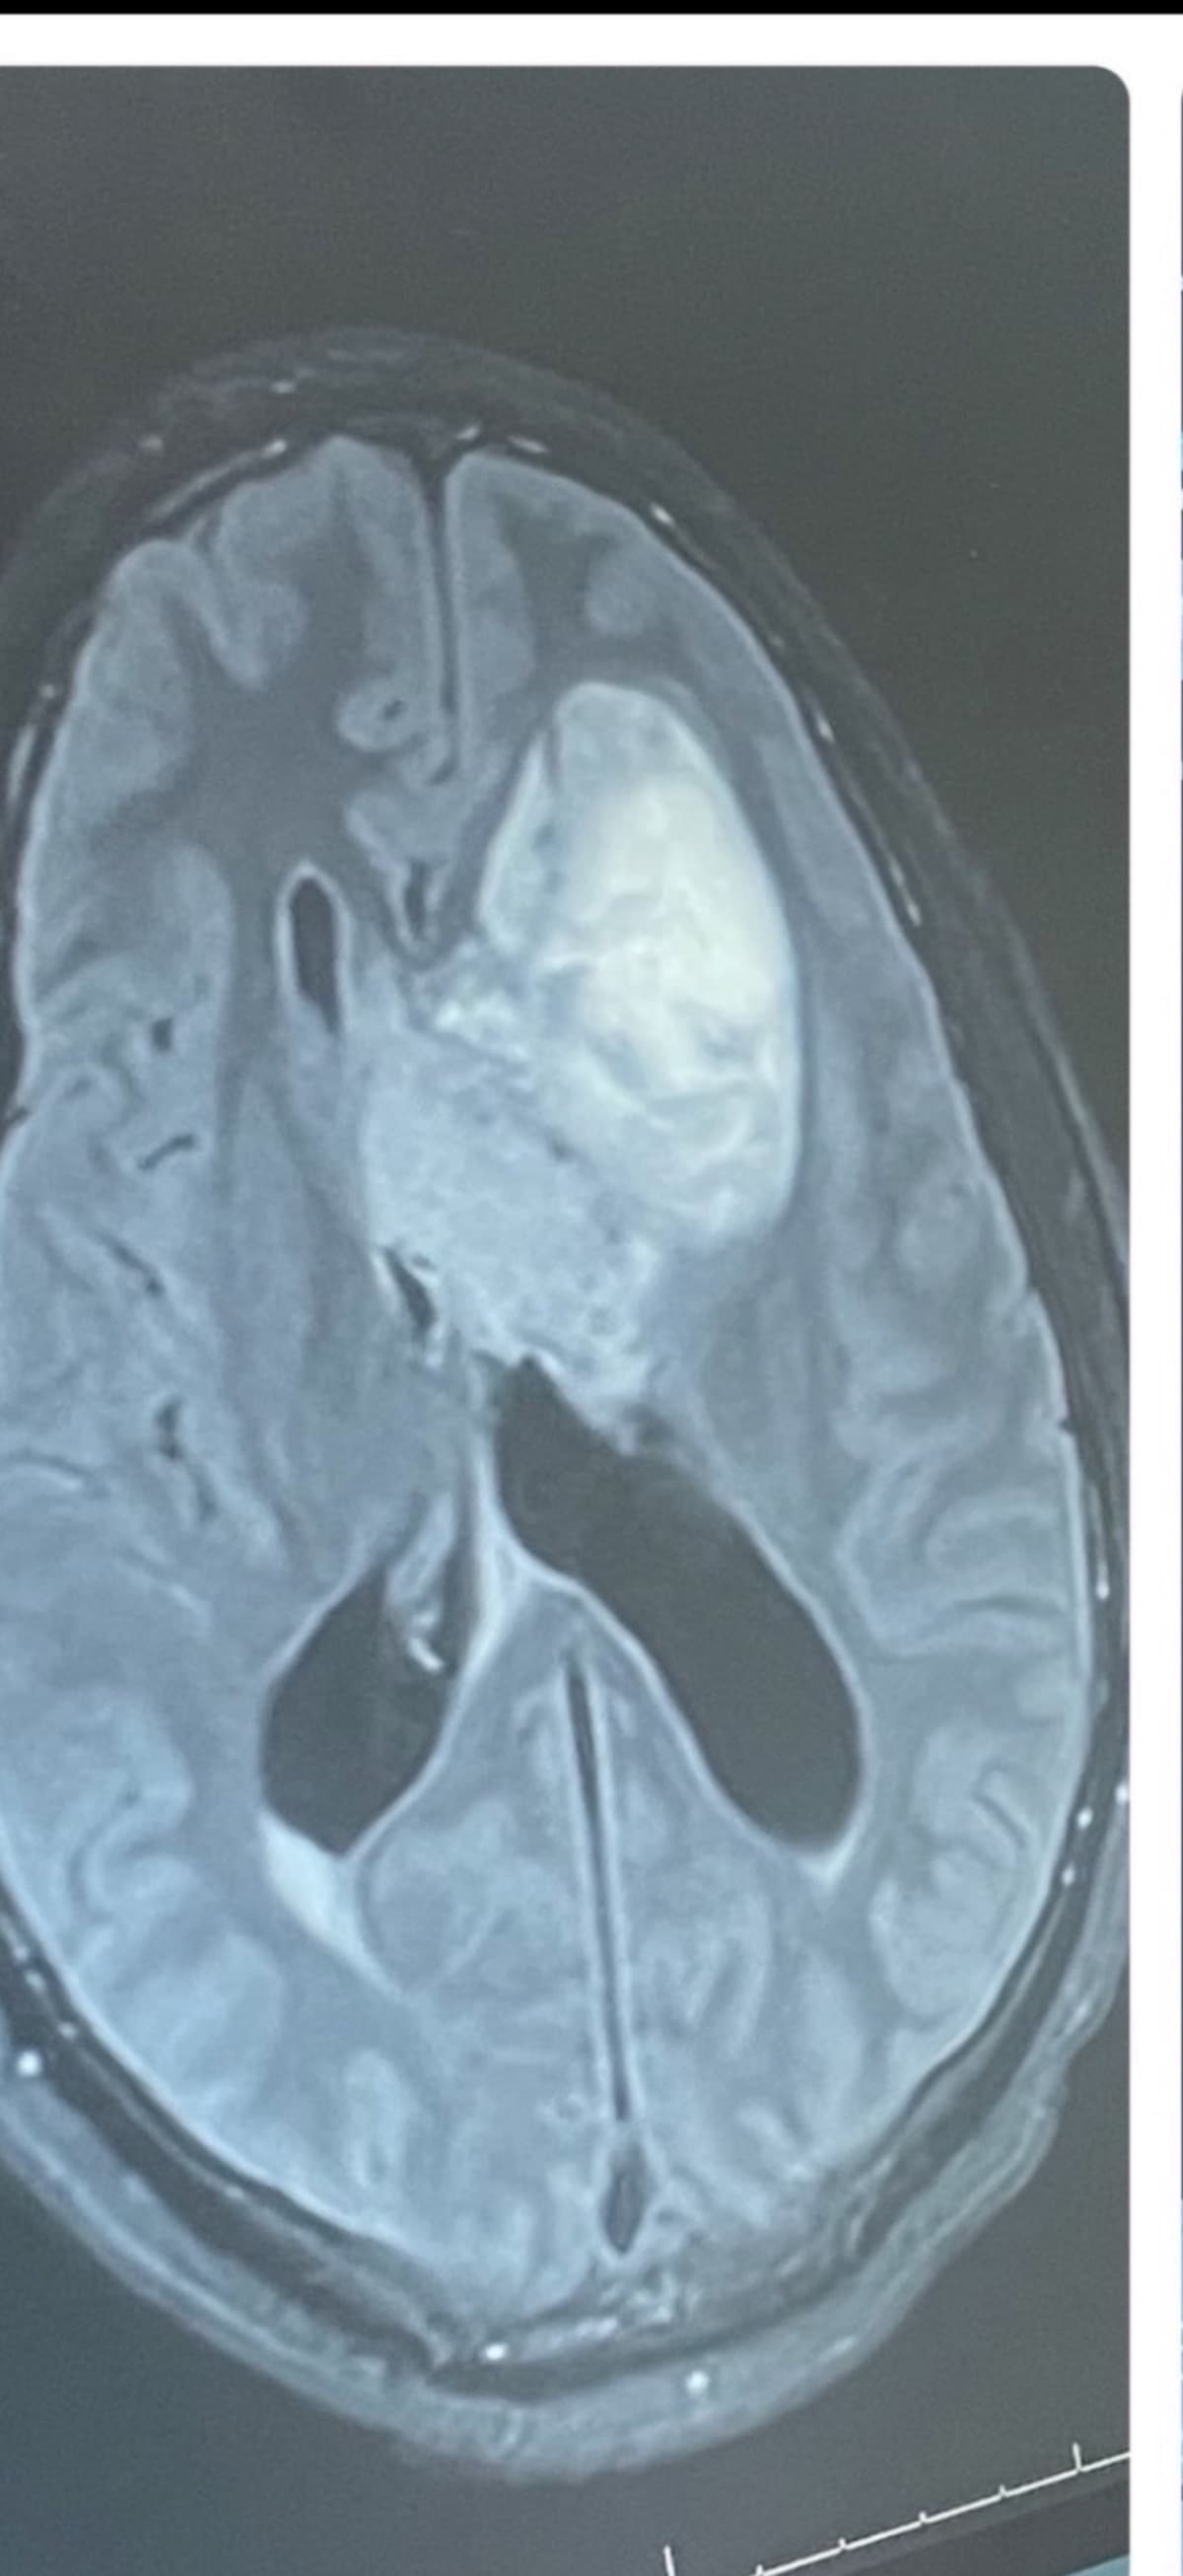

In 2016, I was in a terrible accident after the purchase of my new vehicle. It was at this particular time that I found out I had a brain tumor (Neurocytoma). I underwent surgery to remove it and was completely fine afterwards. I visited my neurosurgeon after my surgery, and things remained well. 2023 came, and my headaches began to recur severely. I made an emergency room visit where I was kept for immediate surgery to remove the Massive tumor pictured below.

Here we are in 2025, my tumor has returned, and I have to undergo another surgery for the (THIRD) time.